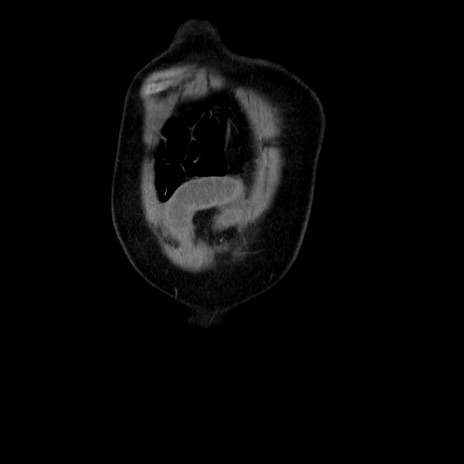

横断像